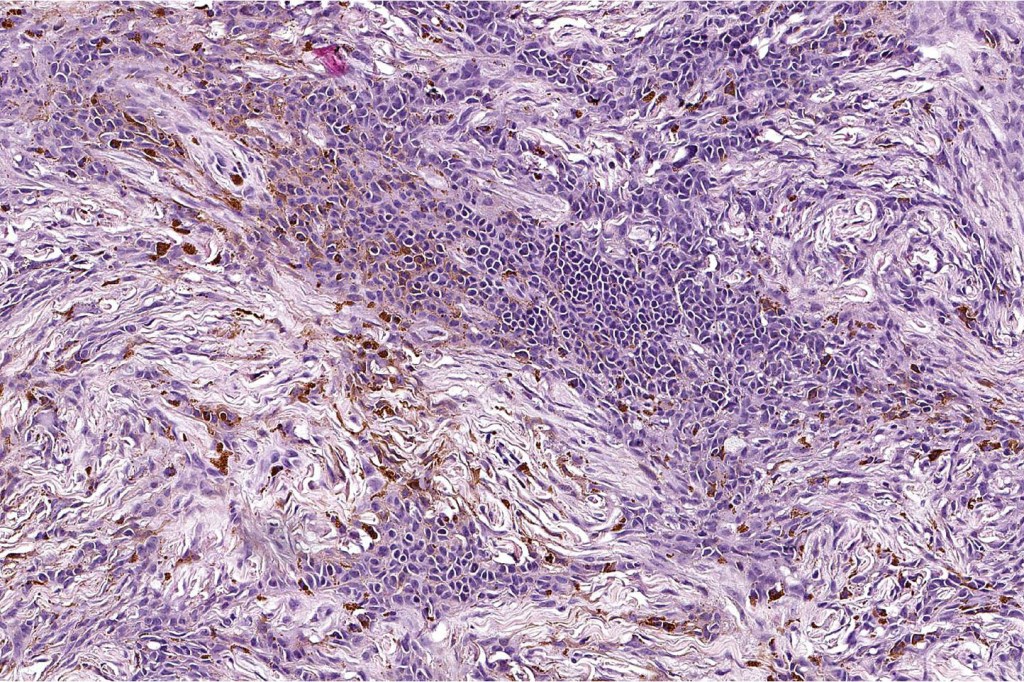

Combined common & deep penetrating nevus